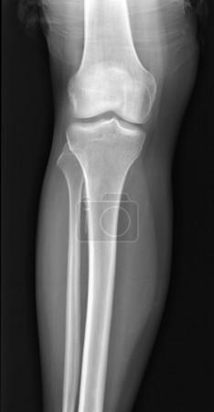

РОЗПІЗНАЙТЕ НА РЕНТГЕНОГРАМІ СУГЛОБ, ЩО СКЛАДАЄТЬСЯ З ТРЬОХ СУГЛОБІВ, ЯКІ МАЮТЬ СПІЛЬНУ КАПСУЛУ.

варіанти відповідей